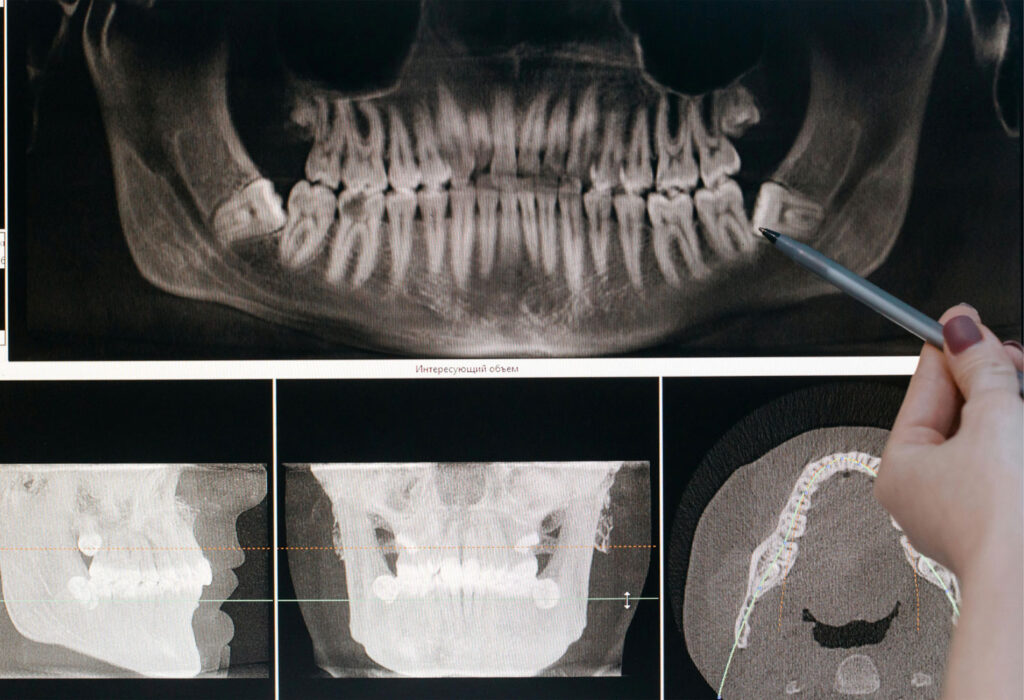

Your dentist can evaluate your wisdom teeth with an exam and X-rays to see if they are coming in properly or if removal is the best option.